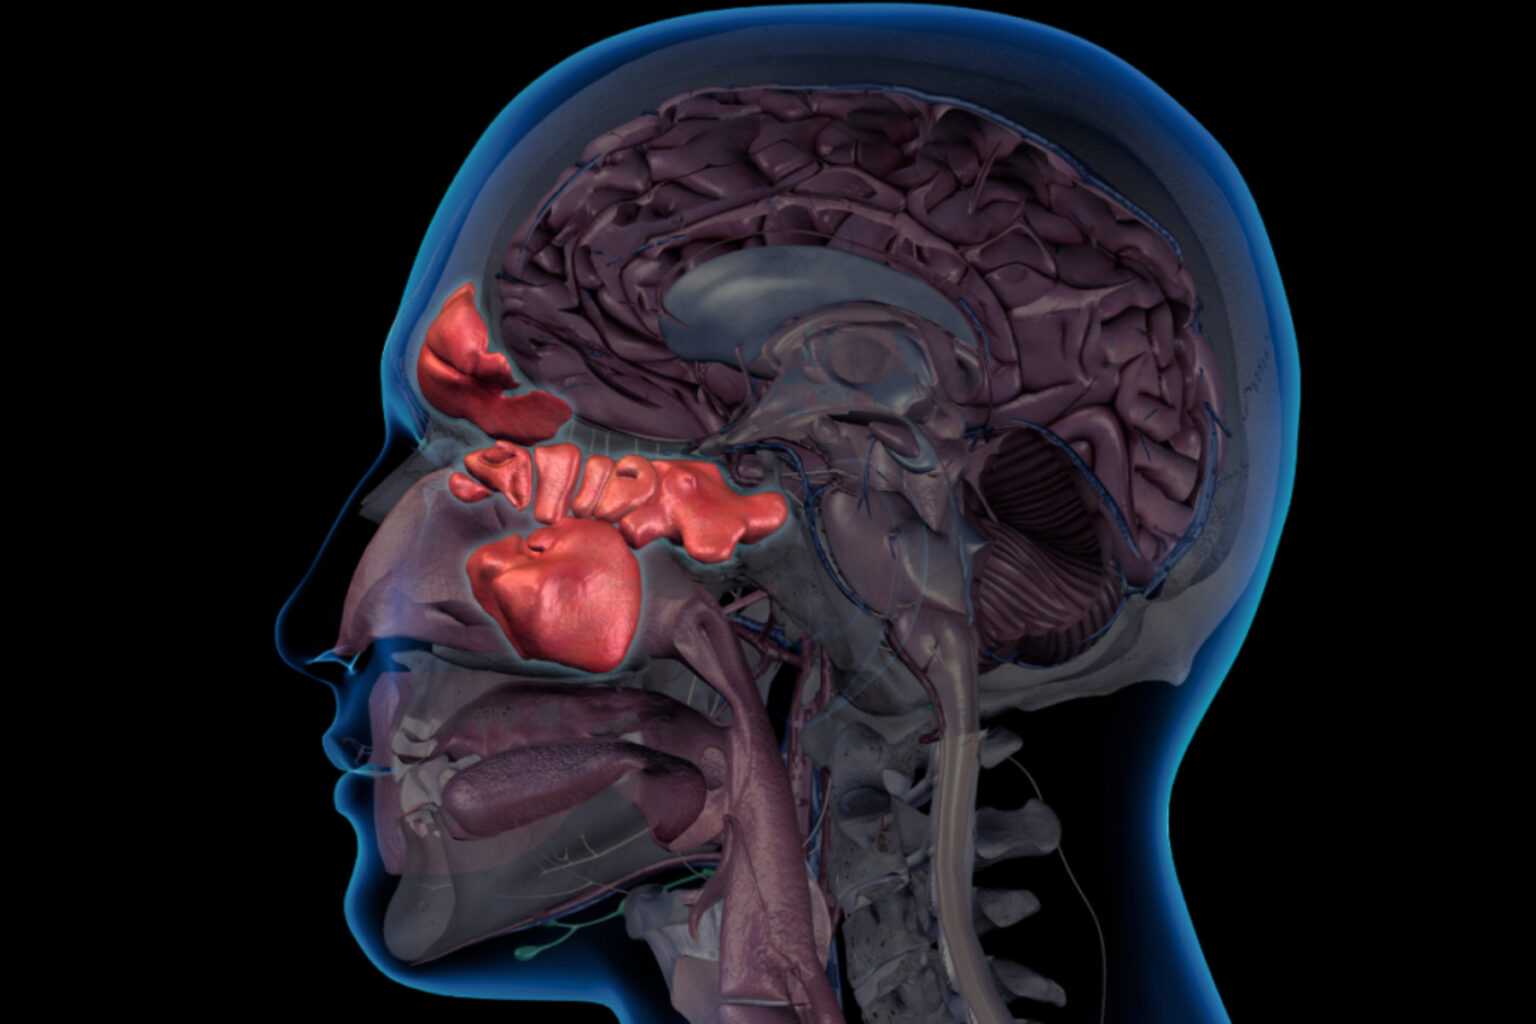

Τα αδενοειδή είναι μικρά κομμάτια ιστού στο πίσω μέρος της μύτης, πάνω από την οροφή του στόματος. Δεν μπορείτε να δείτε τα αδενοειδή ενός ατόμου κοιτάζοντας στο στόμα του. Τα αδενοειδή είναι μέρος του ανοσοποιητικού συστήματος, το οποίο βοηθά στην καταπολέμηση των λοιμώξεων και προστατεύει το σώμα από βακτήρια και ιούς. Τα αδενοειδή είναι μεγαλύτερα όταν είσαι παιδί. Στη συνέχεια αρχίζουν να συρρικνώνονται και συνήθως εξαφανίζονται μέχρι να ενηλικιωθείς.

Οι αδενοειδείς εκβλαστήσεις ενός παιδιού μπορεί μερικές φορές να διογκωθούν ή να διευρυνθούν. Αυτό μπορεί να συμβεί μετά από βακτηριακή ή ιογενή λοίμωξη ή αφού μια ουσία προκαλέσει αλλεργική αντίδραση. Στις περισσότερες περιπτώσεις, τα διογκωμένα αδενοειδή προκαλούν μόνο ήπια ενόχληση και δεν χρειάζεται θεραπεία. Ωστόσο, σε ορισμένα παιδιά, μπορεί να προκαλέσει σοβαρή ενόχληση και να επηρεάσει την καθημερινότητά τους. Τα αδενοειδή μπορεί να χρειαστεί να αφαιρεθούν εάν το παιδί σας έχει: